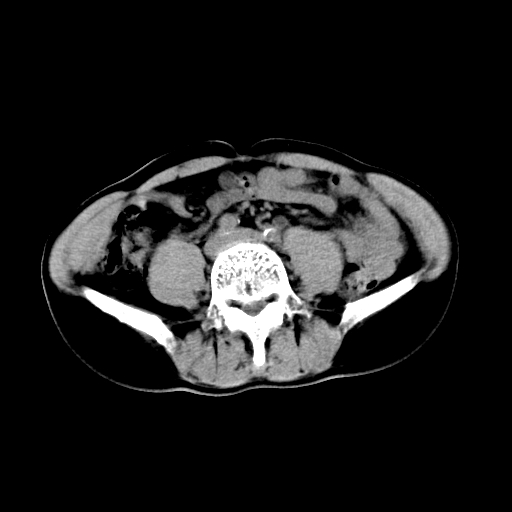

男,47岁,左输尿管结石碎石治疗后10余日。彩超示:左输尿管下段狭窄、输尿管积水。请各位讨论一下左输尿管下段结石还是静脉石?

两侧髂总动脉壁斑状及点状钙化.左侧输尿管行经与左髂总动脉相交后见高密度影,且下段输尿管管腔未见扩张,应该要考虑结石伴以上输尿管及肾盂积水.但右侧结节状高密度影,也应该是结石吧!那以上输尿管未见扩张呢!因此静脉结石可能性也较大.请问楼主碎石前左侧输尿管结石位置.

虽左侧有轻度肾盂积水但不支持结石。1结石边周应该有软组织包绕呈晕征。2钙化点前面见输尿管影也不支持是结石。3彩超没提结石。建议超生复查。

输尿管先位于腹部,后进入盆腔,最后斜穿膀胱壁开口于膀胱,因此,临床上常将输尿管分为腹段、盆段和壁内段。第1个狭窄:在肾盂与输尿管移行处。第2个狭窄:在跨过髂血管处。第3个狭窄:在穿过膀胱壁处。这些狭窄是结石容易滞留的部位。

建议:把输尿管、膀胱扫全,除外输尿管下端结石,必要时强化或泌尿系造影除外其他.

左侧输尿管有轻度扩张伴有肾盂积水,输尿管下段周围的高密度影不象在输尿管内。

同意,不支持结石。(因显示该高密度影前见扩张输尿管影,另外两侧对称显示)。

左侧高密度影在左侧输尿管的内侧方,所以不考虑输尿管结石.